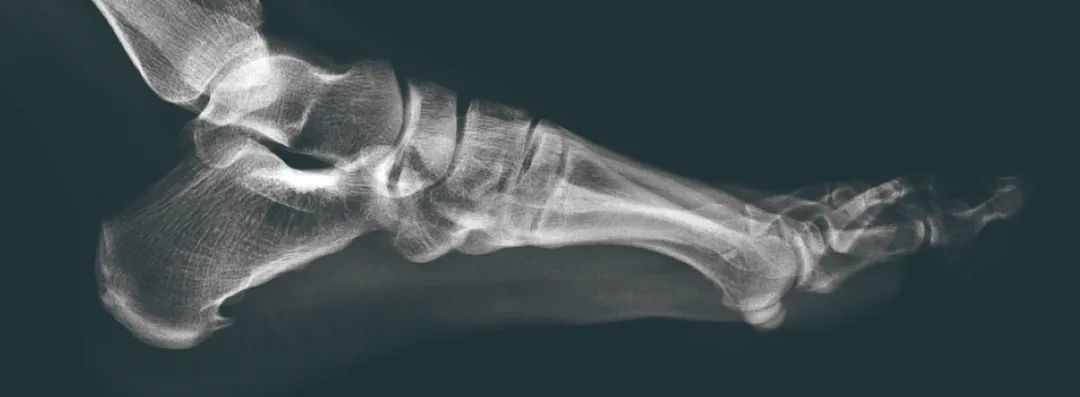

由于无法用活人来做实验,所以研究人员找来了8具尸体。这些脚的大小从37码到43码,然后把尸体直立起来,让汽车从脚背碾过。实验的车辆重达1.45吨——这就是普通小汽车的重量。在车轱辘压过脚之后,研究人员对脚进行了X光检查和切片分析以及其他检验,随后发现无论穿什么样的鞋,脚受的只是皮外伤,而且仅限于被压部分裸露的脚,而所有脚的脚骨没有任何问题。